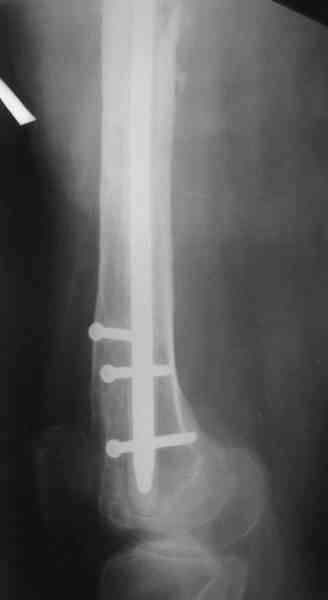

В настоящее время наш пациент ( см. http://weborto.net/forum/1177351385/) ходит с одним костылем. У него периодически открывается свищ на задне-наружной поверхности бедра с умеренным серозно-гнойным отделяемым. Температура тела и анализы нормальные. На рентгенограммах имеются признаки консолидации ложного сустава.

1, 2, 3, 4 - рентгенограммы бедра от 8 августа этого года (через четыре месяца после операции);